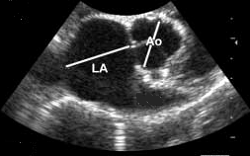

Radiography (x-ray) is used to determine if the heart is enlarged

(particularly the left atrium and left ventricle), if the veins from the

lungs to the heart are distended, or if fluid is beginning to develop in the

lungs.* X-rays also will show any enlargement of

the pulmonary vein, a classic symptom of congestive heart failure (CHF).

*X-ray is the best diagnostic device for detecting fluid in the dog's lungs. See below.

The VHS is not intended to diagnose CHF. It's purpose is to enable veterinarians to more accurately determine enlargement of the heart (called cardiomegaly or dilation) and the progression at which the enlargement is occurring, which usually is due to MVD. However, since MVD normally initially causes only the left atrium (LA) to enlarge, the VHS method is not precise enough to measure only the size of the LA. See for example, the x-ray at left, which shows that the VHS measurements entirely miss the bulbous enlarged LA in the upper right corner of the heart. (Image from Hezzell, 2018.)